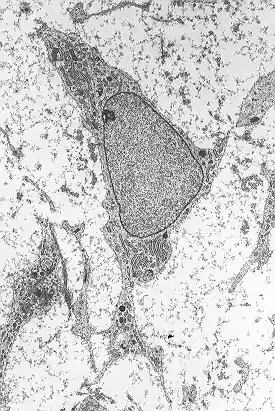

Las células madre de la mesénquima se caracterizan morfológicamente por ser células pequeñas, largas y estrechas con pocos procesos celulares. En el interior se encuentra un núcleo grande y redondo con un nucléolo prominente, rodeado de finas partículas de cromatina que delimitan y diferencian el núcleo claramente. El cuerpo celular contiene además compartimentos celulares como el aparato de Golgi, retículo endoplasmático rugoso, mitocondrias y polirribosomas. Estas células se encuentran bastante dispersas y la matriz extracelular adyacente está formada por algunas fibrillas reticulares, careciendo, sin embargo, de otro tipo de fibrillas de colágeno.[8][9]

- ↑ Netter, Frank H. (1987), Musculoskeletal system: anatomy, physiology, and metabolic disorders. Summit, New Jersey: Ciba-Geigy Corporation ISBN 0-914168-88-6, p.134

- ↑ Brighton, Carl T. and Robert M. Hunt (1991), "Early histologic and ultrastructural changes in medullary fracture callus", Journal of Bone and Joint Surgery, 73-A (6): 832-847